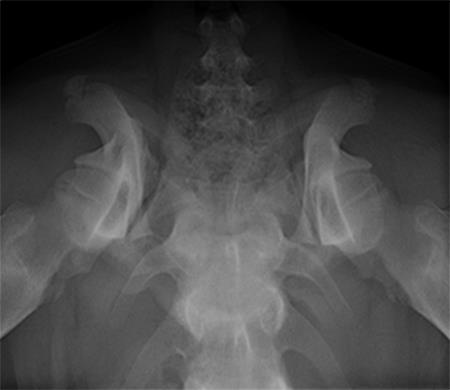

A 4-month-old female boxer puppy weighing 15.0 kg presented with bilateral hind limb weakness and reluctance to walk. Physical examination revealed bilateral hip instability (positive Ortolani sign) and severe pain on full extension of the hips. The neurological exam was normal. The radiographs revealed bilateral hip subluxation and a distraction index of 0.65 of the right hip and 0.6 of the left hip (Fig 7). Very mild osteoarthritis was seen and femoral head coverage by the dorsal acetabular rim was good (Fig 8). Angles of subluxation (10° R and 20° L) and reduction (30° R and 40° L) of the hips were measured under anesthesia.